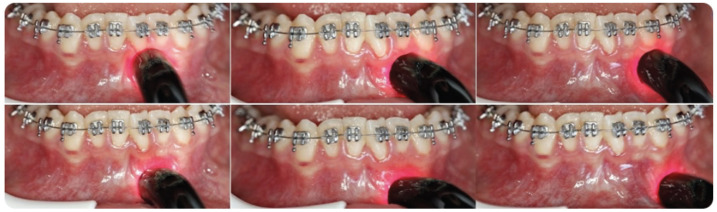

Methods: This double-blinded, parallel, randomized clinical trial included 30 participants who were randomly assigned to the laser group or the control group, with Little's irregularity index of 4-8 mm in the mandibular canine-canine region. Nickel-titanium archwires measuring 0.012 inches were tied with elastomeric ligatures and changed every 14 days throughout the leveling process. The leveling duration was recorded in days, from the bonding application to the end of leveling. Irradiation was performed at an 810-nm wavelength using a gallium-aluminum-arsenide diode laser device with a power output of 100 mW and an energy density of 8 J/cm². Laser applications were performed after archwire ligation (day 0), on days 3, 7, and 14 and every 14 days until leveling was completed. The leveling duration was calculated, and pain levels were evaluated using a visual analogue scale (VAS) after archwire ligation (hour 0), at hours 2 and 6 and on days 1, 3, 7, 14, and 21.

Abstract Image